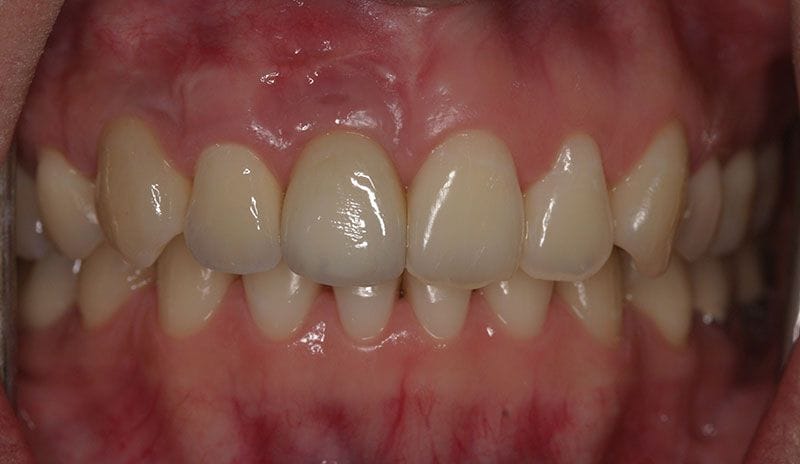

陳小姐是一位美貌與才氣兼具的事業女強人,在一次晚宴中,已經做了十多年的門牙假牙脫落,陳小姐緊急求助黃醫師,立刻進行"立即式植牙" ,將已經蛀壞的牙根拔除,植入人工牙根,再做上美觀的假牙,讓陳小姐無後顧之憂的面對明日的工作。

治療後